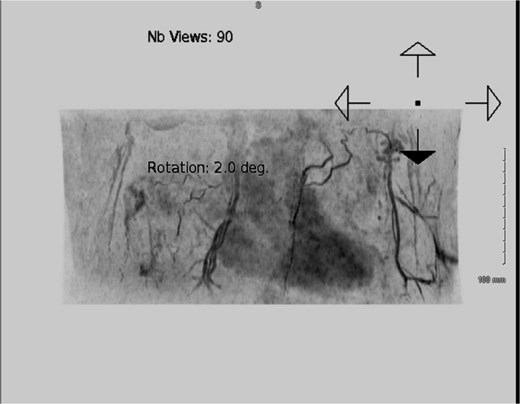

Given her previous loco-regional operations, the deep inferior epigastric artery perforator (DIEP) flap was deemed the most reliable source of skin and volume. An infero-medial surgical access was believed to be the safest approach (Fig. 5) and would enable a reconstruction with a right-sided DIEP flap, buoy skin paddle (Figs 6 and 7), following scar excision, capsulectomy, and explantation (Fig. 6). End-to-end anastomoses with the internal mammary vessels in the 2nd space were achieved, along with augmenting the venous drainage with a retrograde superior inferior epigastric vein-internal mammary vein (SIEV-IMV) anastomosis. Her recovery was complicated by basal atelectasis and pneumonia, causing post-operative delirium, before being discharged on the 8th postoperative day.

Pre-operative computed tomography (CT) angiography demonstrated robust vasculature perfusing the superior and lateral margins of the right breast, suggesting the planned infero-medial access incision would not de-vascularize the remaining breast tissue.